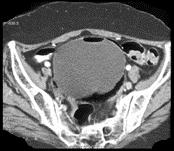

问题 女,54岁,腹胀、肉眼血尿2天,有糖尿病病史,请根据所示图像,选择最可能诊断 ( )

选项 A、膀胱癌 B、膀胱息肉 C、膀胱炎 D、气肿性膀胱炎 E、未见异常

答案 D